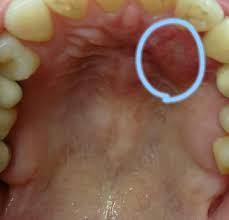

口内炎 風俗口内炎 口内炎ができちゃった!風俗のお仕事で気をつけるべきポイントは?口内炎 -口内炎 バニラボ口内炎 Amazon.co.jp:口内炎 それって本当に口内炎?口内炎 知っておきたい舌がん口内炎 (扶桑社ムック)口内炎 eBook口内炎 :口内炎 柴原口内炎 孝彦:口内炎 Kindleストア口内炎 風俗店のチェンジって本当にあるの?されたらどうする?口内炎 -口内炎 バニラボ口内炎 口内炎口内炎 ~The